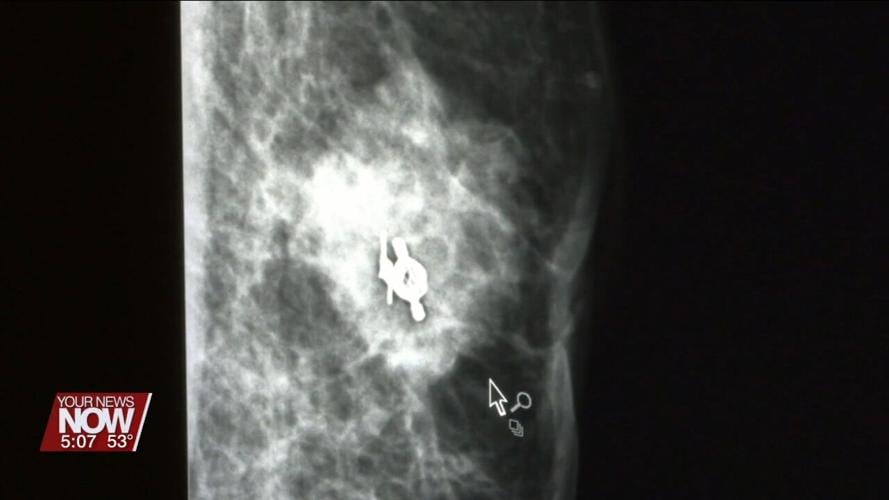

Over time, the lump grew larger and became painful. Eventually, Brian had it checked out and was stunned to learn he had breast cancer.

Brian drove ninety minutes from his home in Pennsylvania to Cleveland Clinic for treatment. There, doctors discovered his cancer had advanced to his lymph nodes and started him on chemotherapy.